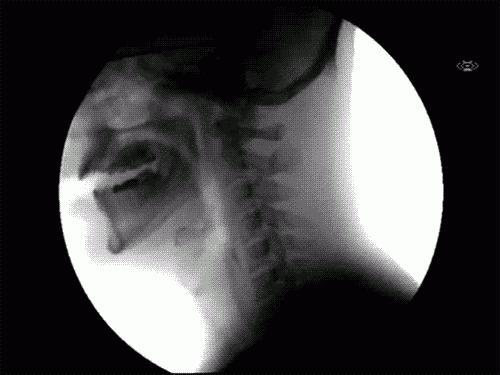

Ce se întâmplă când înghiţi